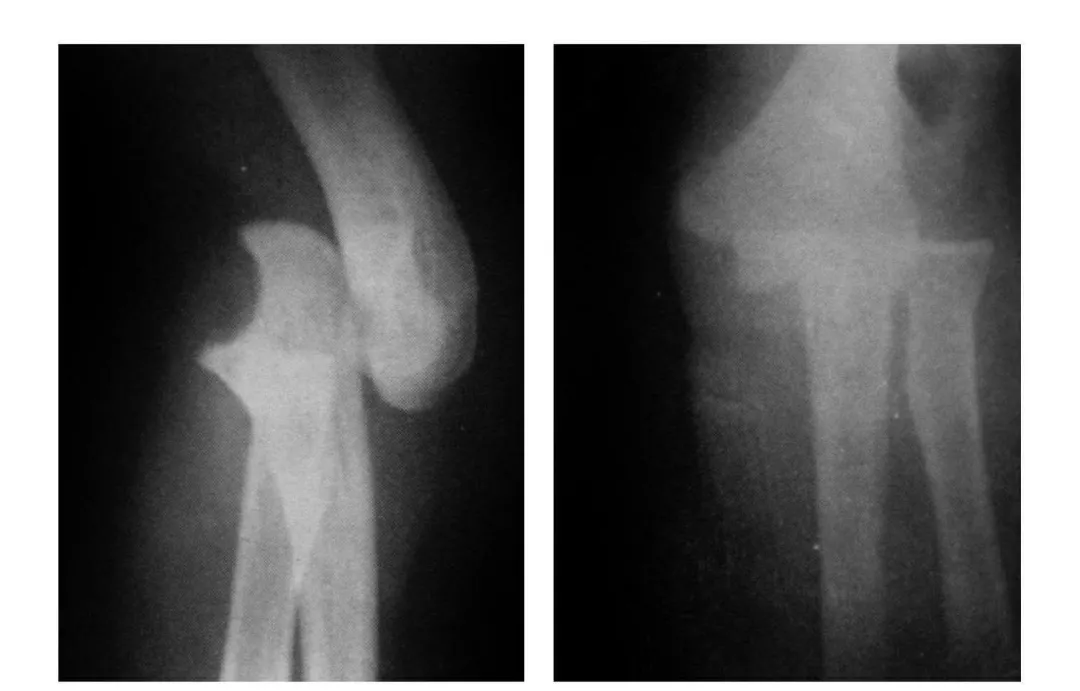

7种肘部损伤x片详细图解

【现病史】 患者于4小时前,不慎摔倒,当即左肘部肿痛畸形伴不

x光片看骨折块似乎很小,骨折移位也不大,可是真的如此吗?

致左肱骨小头粉碎性骨折,入院6天,肘部肿胀减轻后行切开复位内固定术